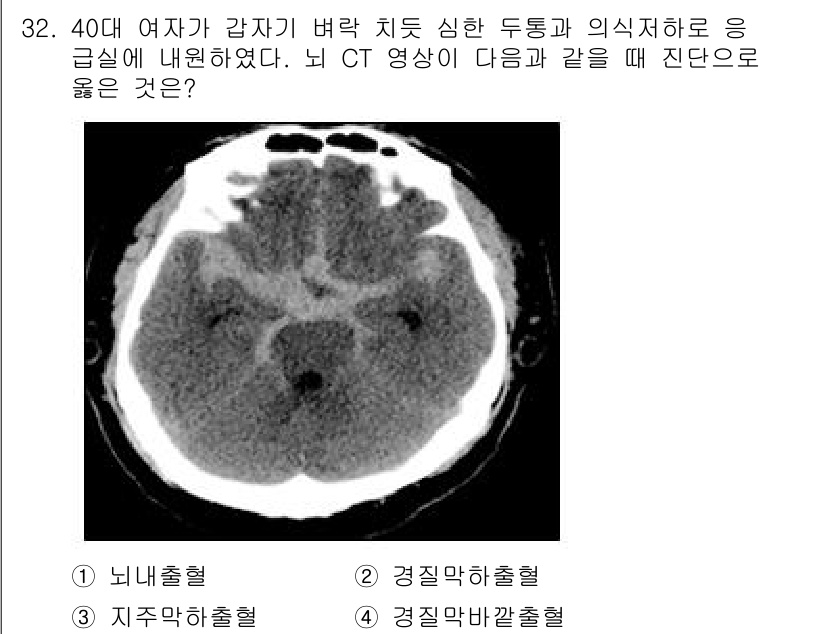

소방공무원(경력)_응급처치학개론

2024년